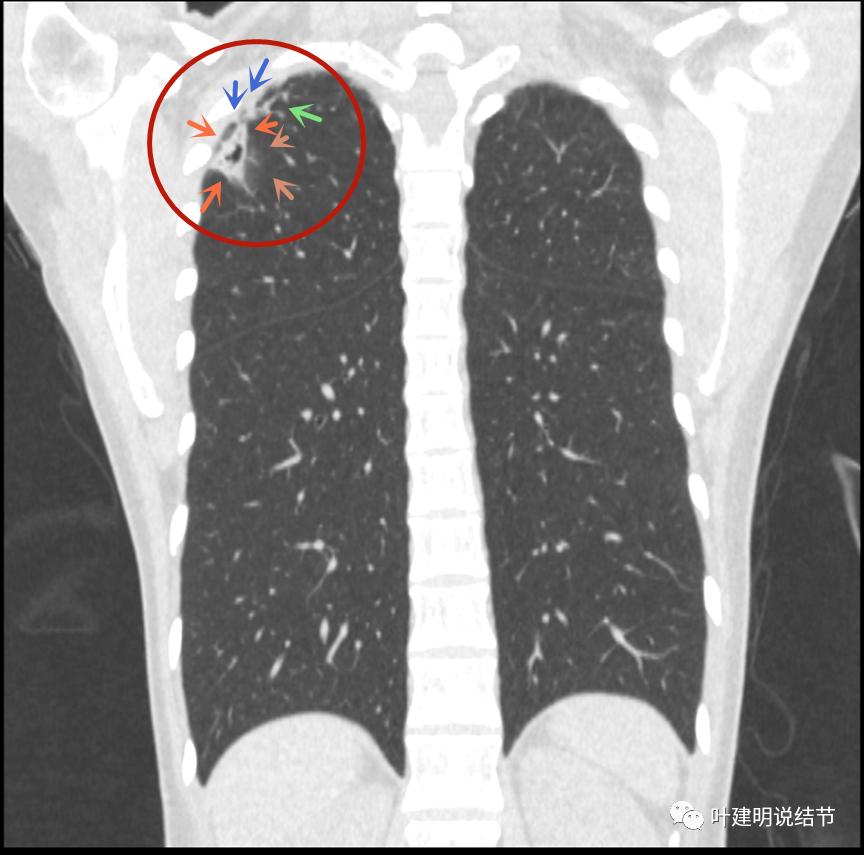

病灶邻近胸膜增厚明显(蓝色箭头);病灶似三角形,边缘平直(桔色箭头);有磨玻璃淡且散,边缘不清(砖色箭头);有卫星病灶(绿色箭头)

有卫星灶,且条索状(绿色箭头),囊壁密度过高(粉色箭头);有空腔征(黄色箭头)

邻近胸膜增厚明显(蓝色箭头),病灶边上部分有淡磨玻璃(砖色箭头)

病灶与胸壁间不似毛刺,像炎性粘连(相连的结构粗细均匀,没有离开病灶后变细,密度较高,邻近胸膜也增厚的);有卫星状(绿色箭头);有淡且散的边缘不清的磨玻璃成分(砖色箭头)

病灶密度高,膨胀性弱,有中间空洞(黄色箭头),囊壁密度过高(粉色箭头);有淡磨玻璃成分(砖色箭头)以及邻近胸膜的明显增厚(蓝色箭头)